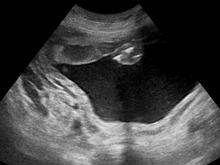

Ultrasound Scan ND 152505 1531230 cr.png

In most cases, the exact cause cannot be identified. A single case may have one or more causes, including intrauterine infection (TORCH), rh-isoimmunisation, or chorioangioma of the placenta. In a multiple gestation pregnancy, the cause of polyhydramnios usually is twin-to-twin transfusion syndrome. Maternal causes include cardiac problems, kidney problems, and maternal diabetes mellitus, which causes fetal hyperglycemia and resulting polyuria (fetal urine is a major source of amniotic fluid).